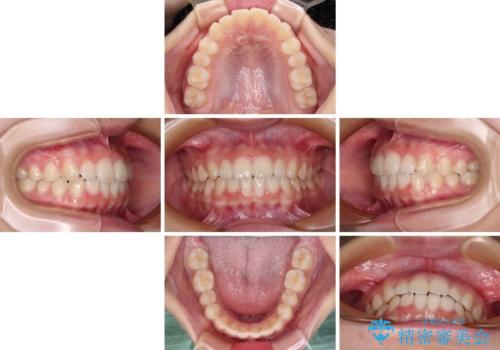

- 前歯のデコボコを気にして来院された高校生の患者様です。

捻れた前歯が前方に飛び出している点も気になっており、目立たない装置を希望されたため、インビザラインを用いて矯正治療を行うこととしました。

上下ともに少し捻れが残っていたため、治療の継続を提案しましたが、本人も親御さんも満足とのことで、治療を終えました。

捻れの改善により突出感も改善されました。